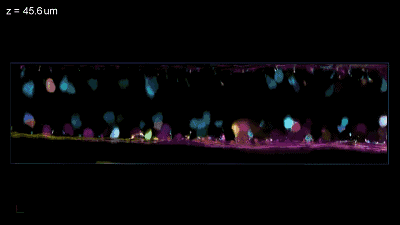

图片

一名53岁女性患者于2008年6月确诊鼻咽癌,随即接受放化疗,治疗3个月后病情得以缓解。

2009年7月发现其癌细胞向右上肺纵膈淋巴转移,后对其进行了右上肺切除术及纵膈淋巴结清扫术。术后,她完成了5个周期的吉西他滨和顺铂(GP)方案化疗及25次放疗。放疗结束后3周,她开始接受DC-CIK治疗,共计5次。

在之后对该患者连续随访13年,未见其肿瘤复发、转移及发生严重不良反应。

该案例展示了术后放化疗联合DC-CIK免疫治疗对鼻咽癌伴肺及纵隔淋巴结转移患者取得了较好的治疗效果,这表明放化疗联合免疫治疗可能是一种安全有效的治疗方案。